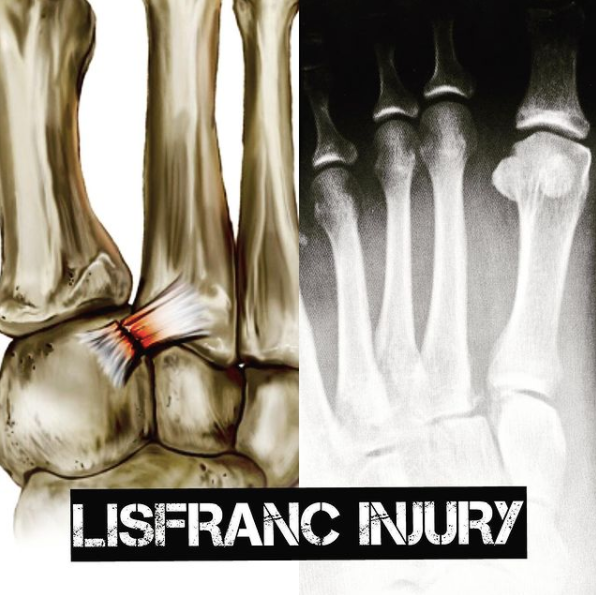

Lesão do ligamento de Lisfranc! Conhece??? Pois é.... Apesar de não ser incomum é uma das lesões mais não diagnósticadas da ortopedia! E seu tratamento é cirurgico na maioria das vezes! Não é incomum um paciente procurar o especialista porque torceu o pé ou caiu um peso sobre seu pé, passou em um Pronto Atendimento, realizaram o RX, mas orientaram tomar remédio para dor....porém a dor não melhorar e a pessoa tem dificuldade para pisar! Esse ligamento faz a conexão do "bloco medial" com o "bloco lateral" do pé e sua lesão, causa uma instabilidade dolorosa no mediopé. Essa instabilidade se não for tratada adequadamente leva a uma degeneração ( artrose) do mediopé a longo prazo que gera muito desconforto. Se você lesionou seu pé, tem muita dor, edema e hematoma na planta do pé, fique atento!!!